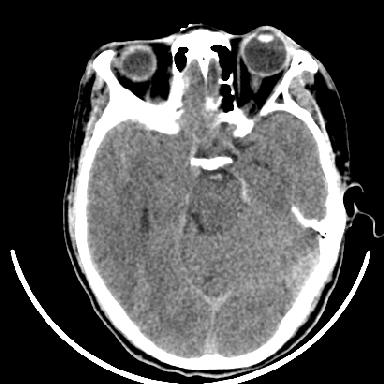

标题: CT6056:脑出血(血管畸形?) [打印本页]

标题: CT6056:脑出血(血管畸形?)

m 40突发头痛左侧偏瘫3小时